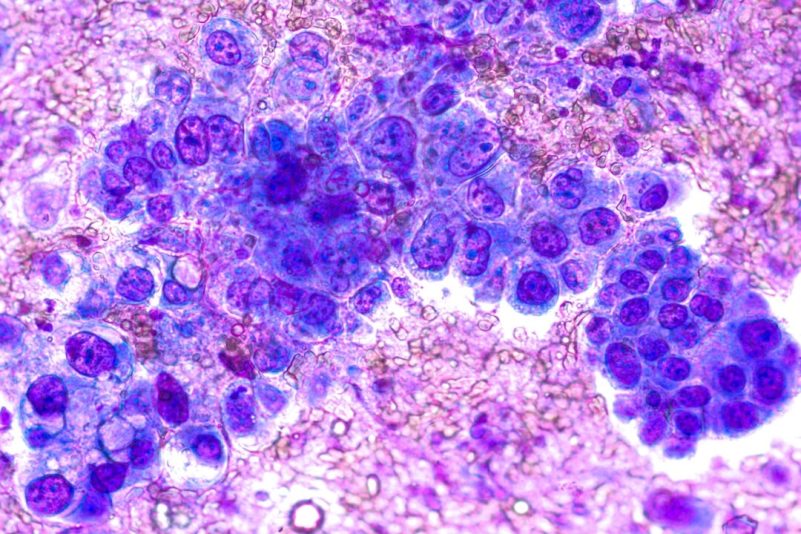

Une étude récente menée par des chercheurs de l’université du Kentucky a identifié le glycogène, une forme de glucose stocké, comme un facteur important dans la progression de l’adénocarcinome pulmonaire, une forme particulièrement agressive de cancer du poumon.

Les résultats, récemment publiés dans Nature Metabolism, suggèrent que des niveaux élevés de glycogène sont liés à une plus grande agressivité des tumeurs de l’adénocarcinome pulmonaire et à une diminution des taux de survie.

Le glycogène lié à un pronostic plus défavorable chez l’homme

L’étude a également porté sur une cohorte complète de 276 patients atteints d’adénocarcinome pulmonaire. Dans ce groupe, l’analyse spatiale a révélé une accumulation significative de glycogène, en particulier dans les régions tumorales. Les niveaux de glycogène étaient plus élevés dans ces zones que dans les tissus sains environnants et dans d’autres types de cancer du poumon.

Les résultats suggèrent que des niveaux élevés de glycogène sont liés à une plus grande agressivité de la tumeur et à des taux de survie plus faibles chez les patients.